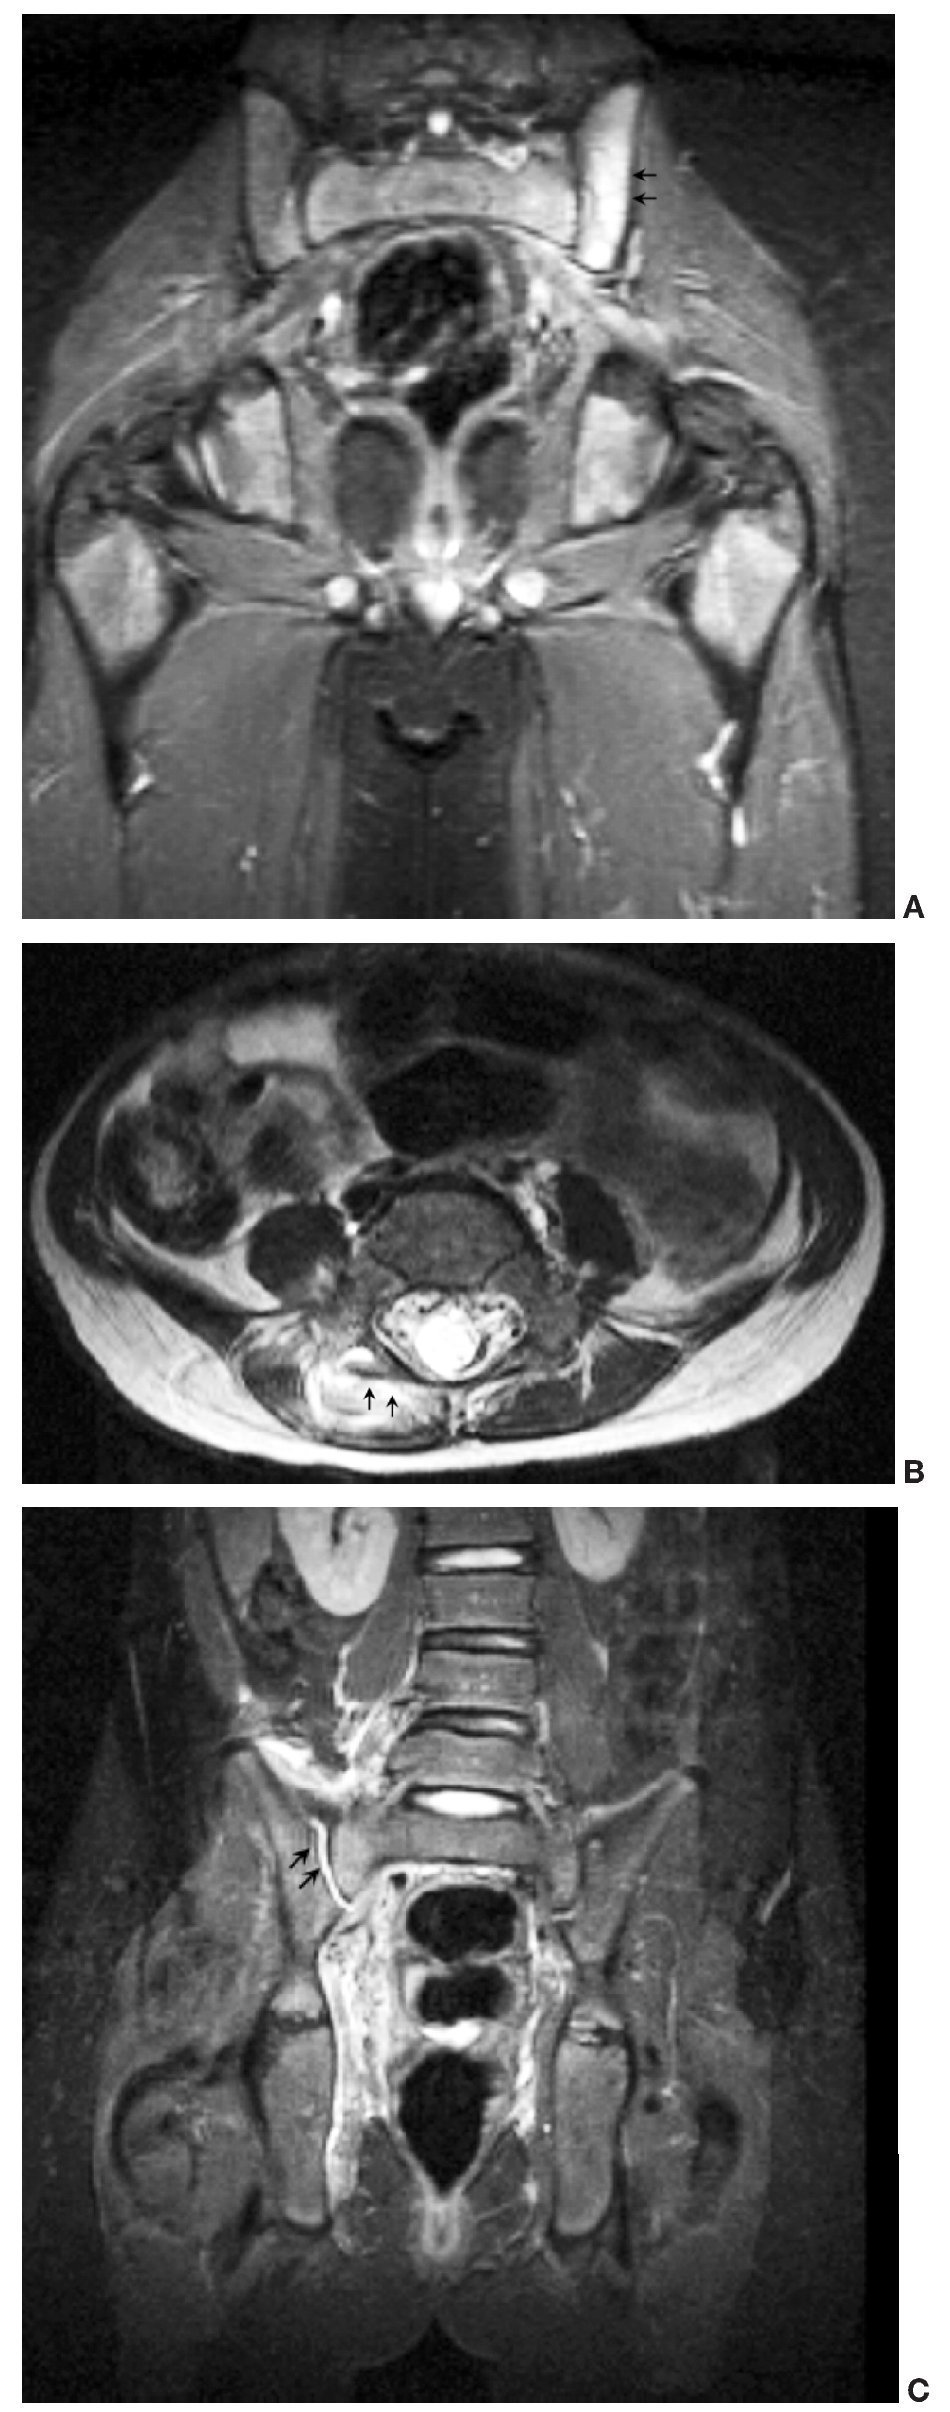

Cuando la ecografía no es concluyente, y persiste una alta sospecha, la técnica de elección es la RM. Spiegel et al12 también demuestran la ventaja de la RM para la identificación de los músculos afectados, los abscesos y la patología subyacente, de forma similar a los hallazgos de nuestra serie (fig. 4). Otros autores como Brigid et al demuestran los hallazgos de la piomiositis en la TC como un aumento de tamaño del músculo afectado, pérdida de la nitidez de los planos musculares y presencia de colecciones hipodensas en caso de abscesos intramusculares; en su serie concluyen que tanto la TC como la RM son útiles para la identificación de los músculos afectados y de abscesos20.

Fig. 4. (A) Afectación osteoarticular. Aumento de señal en el hueso ilíaco izquierdo en secuencia coronal STIR. (B) Afectación osteoarticular. Secuencia axial FSE T2: afectación de la articulación interapofisaria con mínimo derrame articular. (C) Afectación osteoarticular. Secuencia coronal STIR: derrame en la articulación sacroilíaca derecha.

La RM contribuye al diagnóstico diferencial de la piomiositis con otras entidades como la artritis séptica, la osteomielitis, la tromboflebitis y el tumor. Asimismo, la administración de gadolinio identifica la presencia de abscesos, siendo de gran utilidad en el caso de que requieran drenaje percutáneo. Las áreas de piomiositis se manifiestan en una fase inicial como zonas heterogéneas y con elevada señal en las secuencias potenciadas en T2 y STIR. En fases tardías, los abscesos se presentan como áreas de baja señal en T1 y alta señal en T2, que realzan de manera periférica tras la administración de gadolinio (fig. 5), hallazgos que coinciden con la serie presentada por Soler et al21. Cambios en la señal del hueso se vieron en 7 de nuestros casos, mientras que una captación gammagráfica positiva sólo se apreció en 4 casos; esto indica que la RM es altamente sensible para identificar la patología ósea subyacente, aunque es difícil diferenciar si estos cambios en la señal del hueso se deben a la presencia real de osteomielitis o a edema reactivo. En estos casos el citrato de galio-67 y los leucocitos marcados con 111In o 99mTc pueden aumentar la sensibilidad y especificidad de la prueba radioisótopica22,23. El citrato de galio administrado por vía intravenosa se fija a la transferrina y se une a la lactoferrina de los leucocitos, e incluso a las propias bacterias, y se acumula en mayor cantidad en los focos inflamatorios y sépticos.

Fig. 5. (A) Fase purulenta. FSE T1 que muestra una zona de baja señal en el obturador externo derecho, sugestiva de pequeño absceso. (B) Fase purulenta; la misma imagen en secuencia STIR que muestra la hiperseñal del absceso. (C) Absceso del músculo psoasilíaco. Resonancia magnética en plano coronal FSE T1 tras la administración de gadolinio intravenoso, que muestra múltiples imágenes hipointensas con realce periférico sugestivas de abscesos.